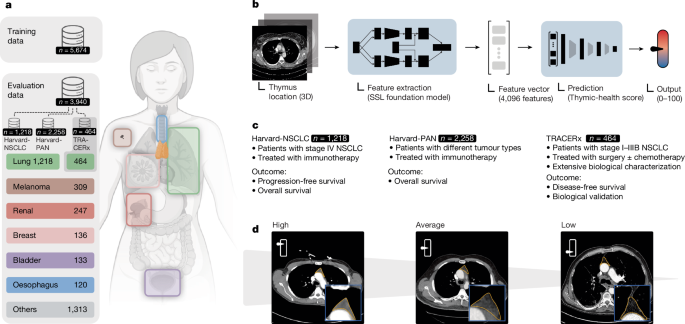

Thymus health is a predictor of lifelong well-being and immunotherapy effectiveness

Nature, Published online: 18 March 2026; doi:10.1038/d41586-026-00633-6It was thought that the thymus serves its purpose for the immune system early in life....

Thymic health and immunotherapy outcomes in patients with cancer - Nature

Nature, Published online: 18 March 2026; doi:10.1038/s41586-026-10243-xA deep-learning approach applied to routine CT scans is used to quantify the health of...

Thymic health consequences in adults - Nature

Nature, Published online: 18 March 2026; doi:10.1038/s41586-026-10242-yAssessing thymic function and health has highlighted the lifelong importance of the th...